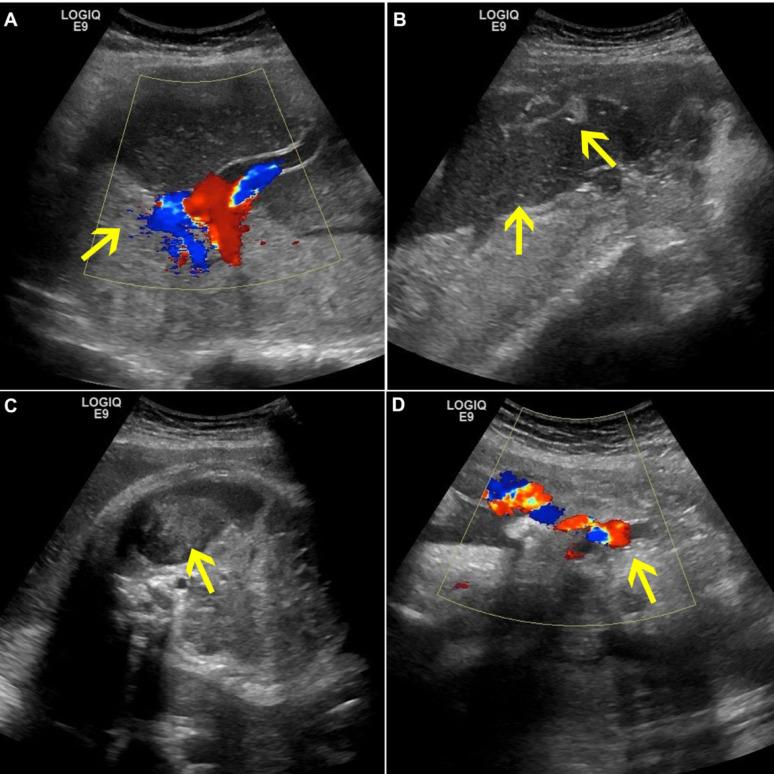

A 35-year-old woman at 37 weeks of gestation who presented with lower abdominal discomfort and decreased fetal movements came to our emergency department. Ultrasound revealed medium-strong echoes in the amniotic fluid and inhomogeneous echoes around the umbilical cord. A Category II fetal heart rate baseline (FHR) tracing, indicative of fetal compromise, along with an elevated MCA-PSV approaching the diagnostic threshold for fetal anemia, suggested ongoing fetal hypoxia or hemorrhage and warranted immediate delivery to mitigate the risk of adverse outcomes. An emergency cesarean section revealed significant intraamniotic hemorrhage and a subamniotic hematoma near the umbilical cord insertion.

一名37周妊娠的35岁女性因下腹部不适和胎动减少前来我院急诊科。超声显示羊水中有中等强度回声,脐带周围回声不均匀。II类胎儿心率基线(FHR)描记图提示胎儿窘迫,同时大脑中动脉收缩期峰值速度(MCA-PSV)升高接近胎儿贫血的诊断阈值,提示胎儿持续缺氧或出血,需要立即分娩以降低不良后果的风险。急诊剖宫产显示羊膜腔内有大量出血,脐带插入处附近有羊膜下血肿。